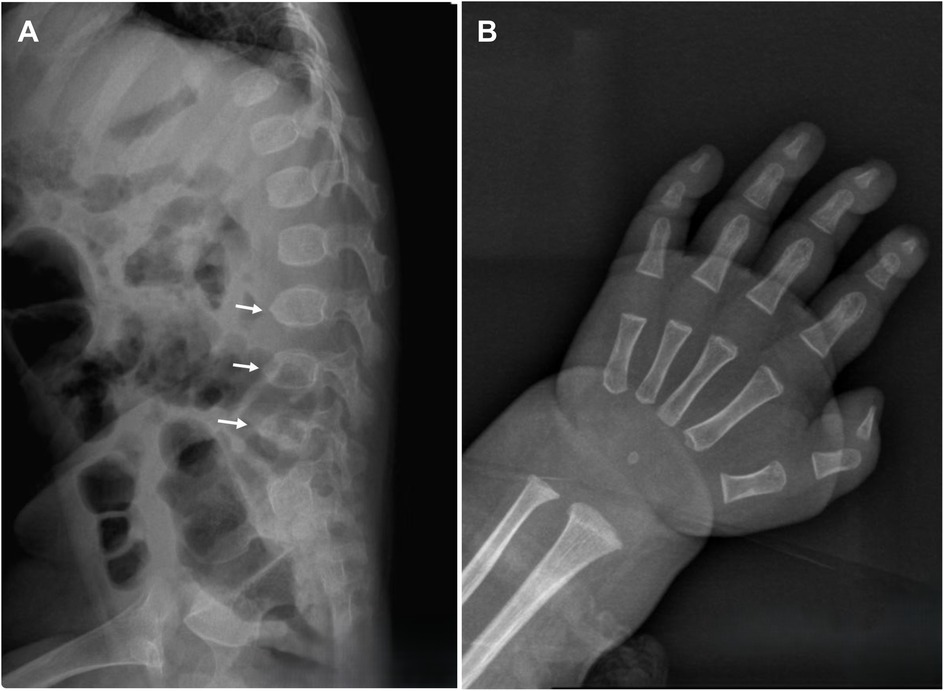

On physical examination, the child demonstrated short stature, severe emaciation, and distinctive craniofacial features, including a broad forehead and cranial dysmorphism (Figures 1A,B). Cardiopulmonary examination revealed no abnormalities, and hepatosplenomegaly was absent throughout the disease course. Cranial magnetic resonance imaging (MRI) revealed skull dysplasia, characterized by a shortened anteroposterior diameter and an elongated left-right diameter, resembling brachycephaly associated with bilateral coronal synostosis (Figures 1C,D). However, the cranial sutures were intact, ruling out true coronal synostosis. Lumbar spine x-ray demonstrated localized lumbar kyphosis and beak-like deformities at the anterior margins of the third, fourth, and fifth lumbar vertebrae (Figure 2A). Bone age assessment at 9 months of age revealed a delay of approximately 0.5 years (Figure 2B).

Figure 2. A Lumbar spine x-ray reveals localized lumbar kyphosis, with beak-like deformities at the anterior edges of the third, fourth, and fifth lumbar vertebrae (indicated by white arrows). (B) Bone age radiograph at 9 months of age shows a delay of approximately 0.5 years.